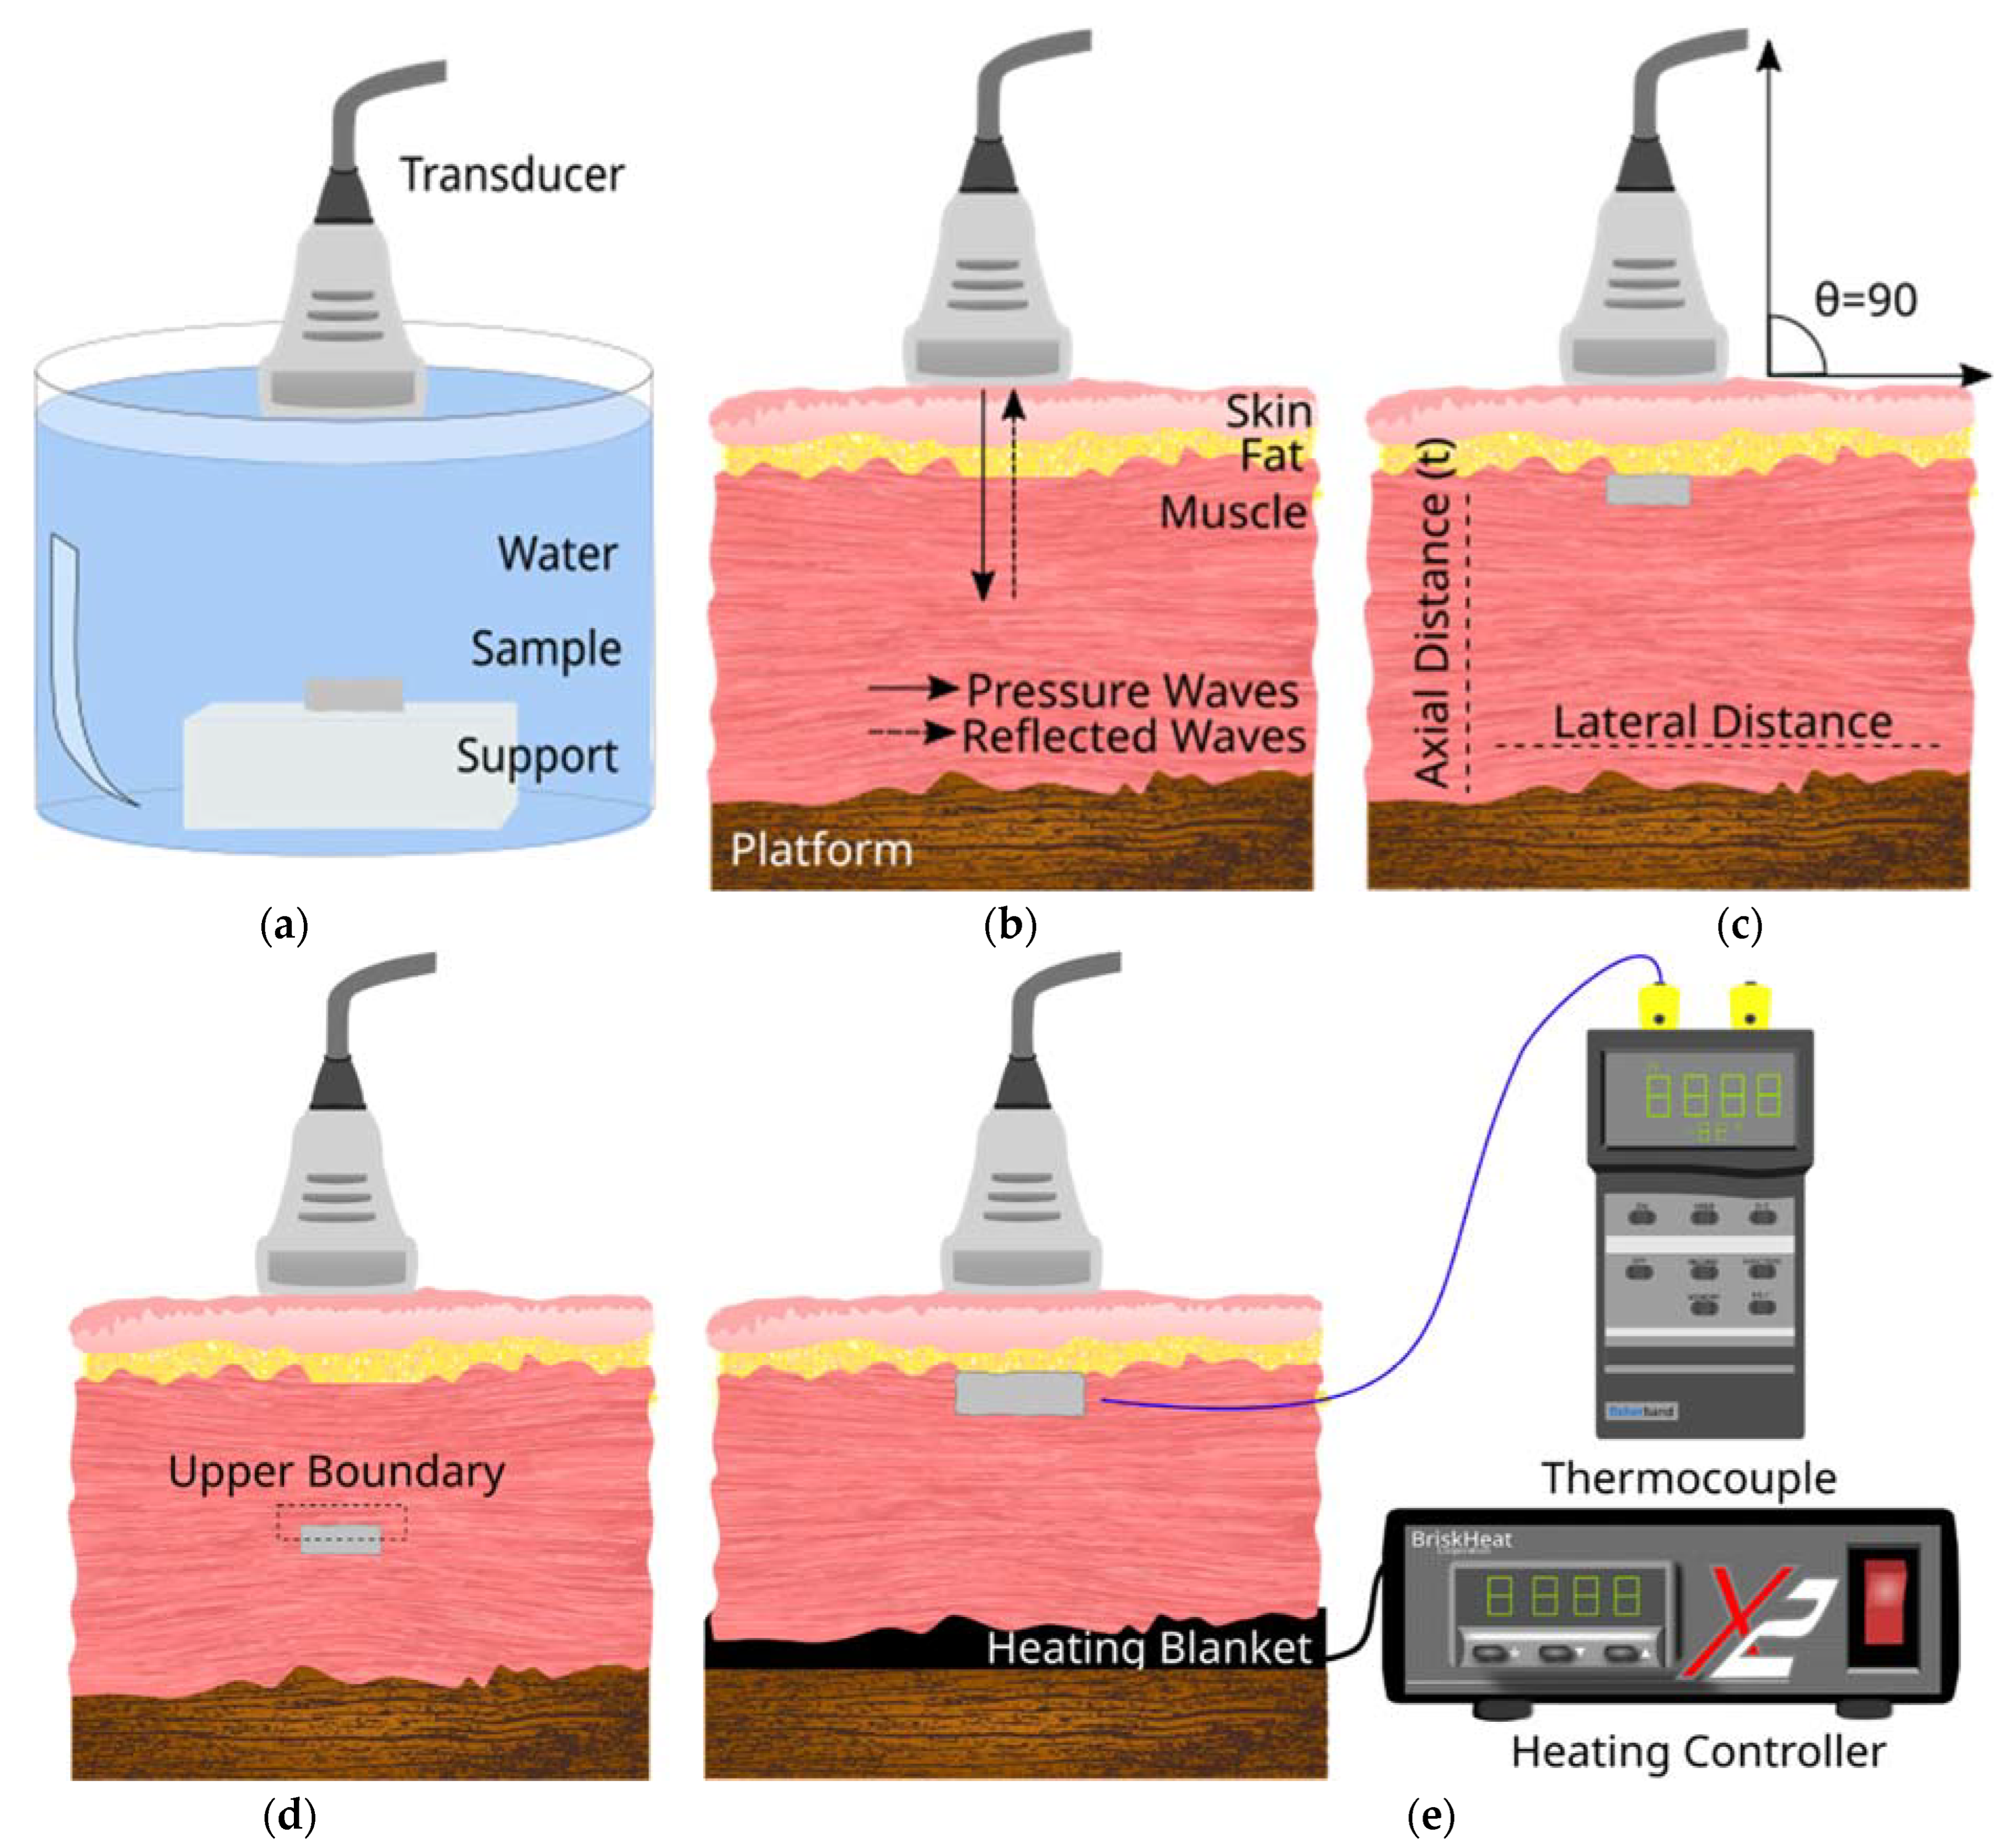

2.3. Experimental Setup for Ultrasound Image Acquisition

2.4. Image Processing and Analysis

2.5. Attenuation Calculation

2.6. Echogenicity